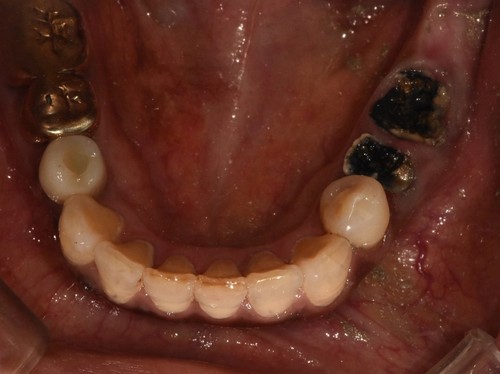

임플란트를 식립한 후에는 통상적으로는 3개월 후에 임플란트 보철물이 들어가는데 환자분의 사정으로 치과 내원을 못 하셔서 약 5개월 후에 오셨는데 왼쪽 아래 치아의 뿌리 부위의 충치가 발견되어서 아래 치아는 발치하면서 식립하는 즉시식립을 해 드렸습니다.

보통 하악에 임플란트 식립하면 2개월 이내에 치아가 들어가는데 마찬가지로 환자분 사정으로 못 오시다가 6개월이 지나서야 위,아래 임플란트 머리가 들어가고 마무리 할수 있었습니다.